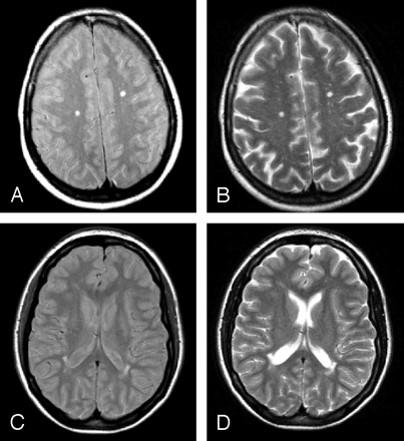

what type of imaging is this and what is being shown

MRI: water dense in MRI

arrow poniting to periventricular damage, which is more likely with high pressure hydrocephalus